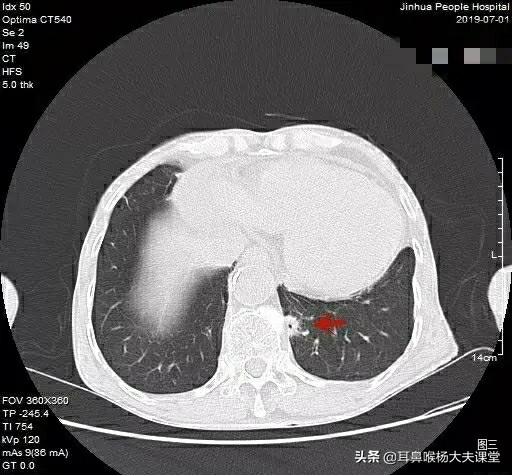

20年前我有一位同事老林被诊断为肺癌,从CT片上看肺部有肿块,因为本身是医疗系统的,有很多熟人,找一些放射科医生、胸外科医生一起阅片,最后一致判断是肺癌,做了手术,传统的开胸手术,以前还没有现在的胸腔镜手术,伤口绵延整个胸部,切除包块病理检查,炎性包块,不是肿瘤,老林哭笑不得,不知是高兴还是悲哀。

还有医院一个病人,唐先生今年53岁,因为发烧咳嗽,经历各种检查折腾,甚至动用了昂贵的pet-ct检查,结果显示右肺有肿块,怀疑是肺癌晚期,建议手术。后来转院到省肿瘤医院,电子气管镜轻松“揪”出元凶,原来气管里是一片长约2.5厘米的干辣椒,医生当场取出干辣椒,常规消炎几天后,唐先生病愈出院。

事后,唐先生才回忆起来,上月他吃饭时,呛到干辣椒,后来就开始莫名其妙的咳嗽、发烧,但做了气管镜都没检查出异样,结果遭了这么多罪!